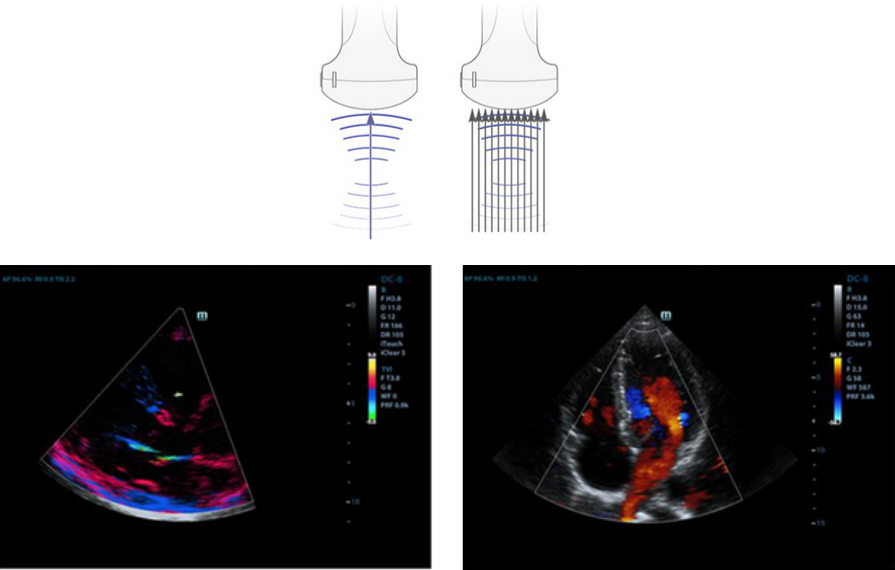

Formaci├│n de haces enriquecida por eco

La formaci├│n de haces enriquecida por eco permite utilizar las se?ales de eco tradicionalmente ignoradas de los haces adyacentes para formar un haz de imagen m├Īs fino y fuerte, lo que permite obtener una mejor resoluci├│n de las im├Īgenes "desenfocadas" y una penetraci├│n de imagen m├Īs profunda.

Formaci├│n de varios haces

Un m├Īximo de 12 asignaciones de tarea para un haz transmitido, lo que permite obtener una excelente resoluci├│n temporal y una velocidad de imagen m├Īs alta.